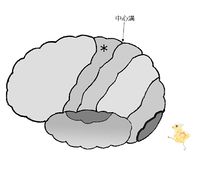

図は、左の大脳皮質を左から見た図です。

中心溝の前にある中心前回には、運動野があります。「手を挙げよう」などの随意的運動の命令は、前頭葉の中心前回に発生し、上肢、肩の筋へ届けられ手が挙がります。

中心溝の後ろにある中心後回には、(皮膚)感覚野があります。頭頂葉の一部です。皮膚から触圧覚・関節の感覚の情報は頭頂葉の中心後回に届いて「触った!」と感じるのです。

大脳皮質の図において、*印は 前頭葉 頭頂葉 後頭葉 側頭葉 である。

大脳皮質の図において、*印は 前頭葉 頭頂葉 後頭葉 側頭葉 である。

大脳皮質の図において、*印は 前頭葉 頭頂葉 後頭葉 側頭葉 である。

大脳皮質の図において、*印は 前頭葉 頭頂葉 後頭葉 側頭葉 である。

大脳皮質の図において、*印は 中心前回 中心後回 である。

大脳皮質の図において、*印は 中心前回 中心後回 である。